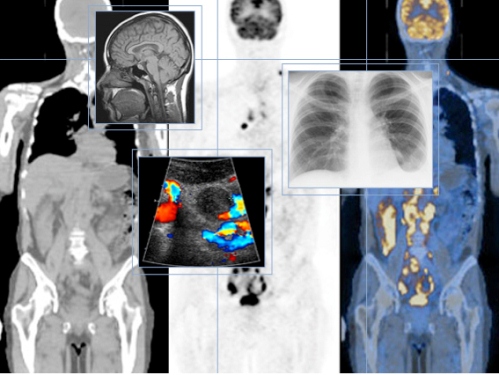

- Ứng dụng trên nhiều thiết bị tạo ảnh

DICOM Data - Echo, Angiogram, IVUS, NM, CT, MRI, Carotid, Vascular.

- Và các dạng sơ đồ, PDF, mẫu báo cáo dạng văn bản (text)

Non DICOM Data - ECG, Treamill, Holter, EP, FFR, CARTO, ABP, Hemodynamic, PDF, MPEG